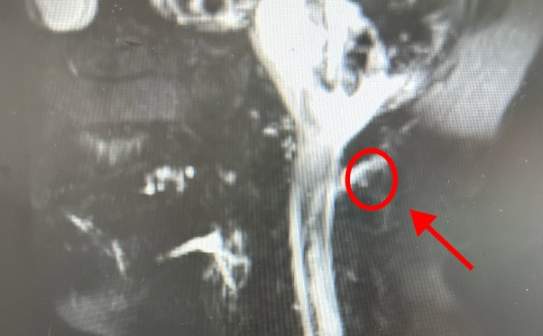

疼痛科副主任医师李庆华认为,林大姐的症状疑似低颅压性头痛。经检查,其颈椎处有明显的漏液。医生表示“是脑脊液漏出导致的低颅压性头痛,且破口位置较高,在颈椎处。”

图源:健康杭州

“临床上,低颅压患者脊椎相应的漏液部分,经常会发现骨刺。”李庆华表示这与生活习惯有很大的关系,低头族要特别当心。